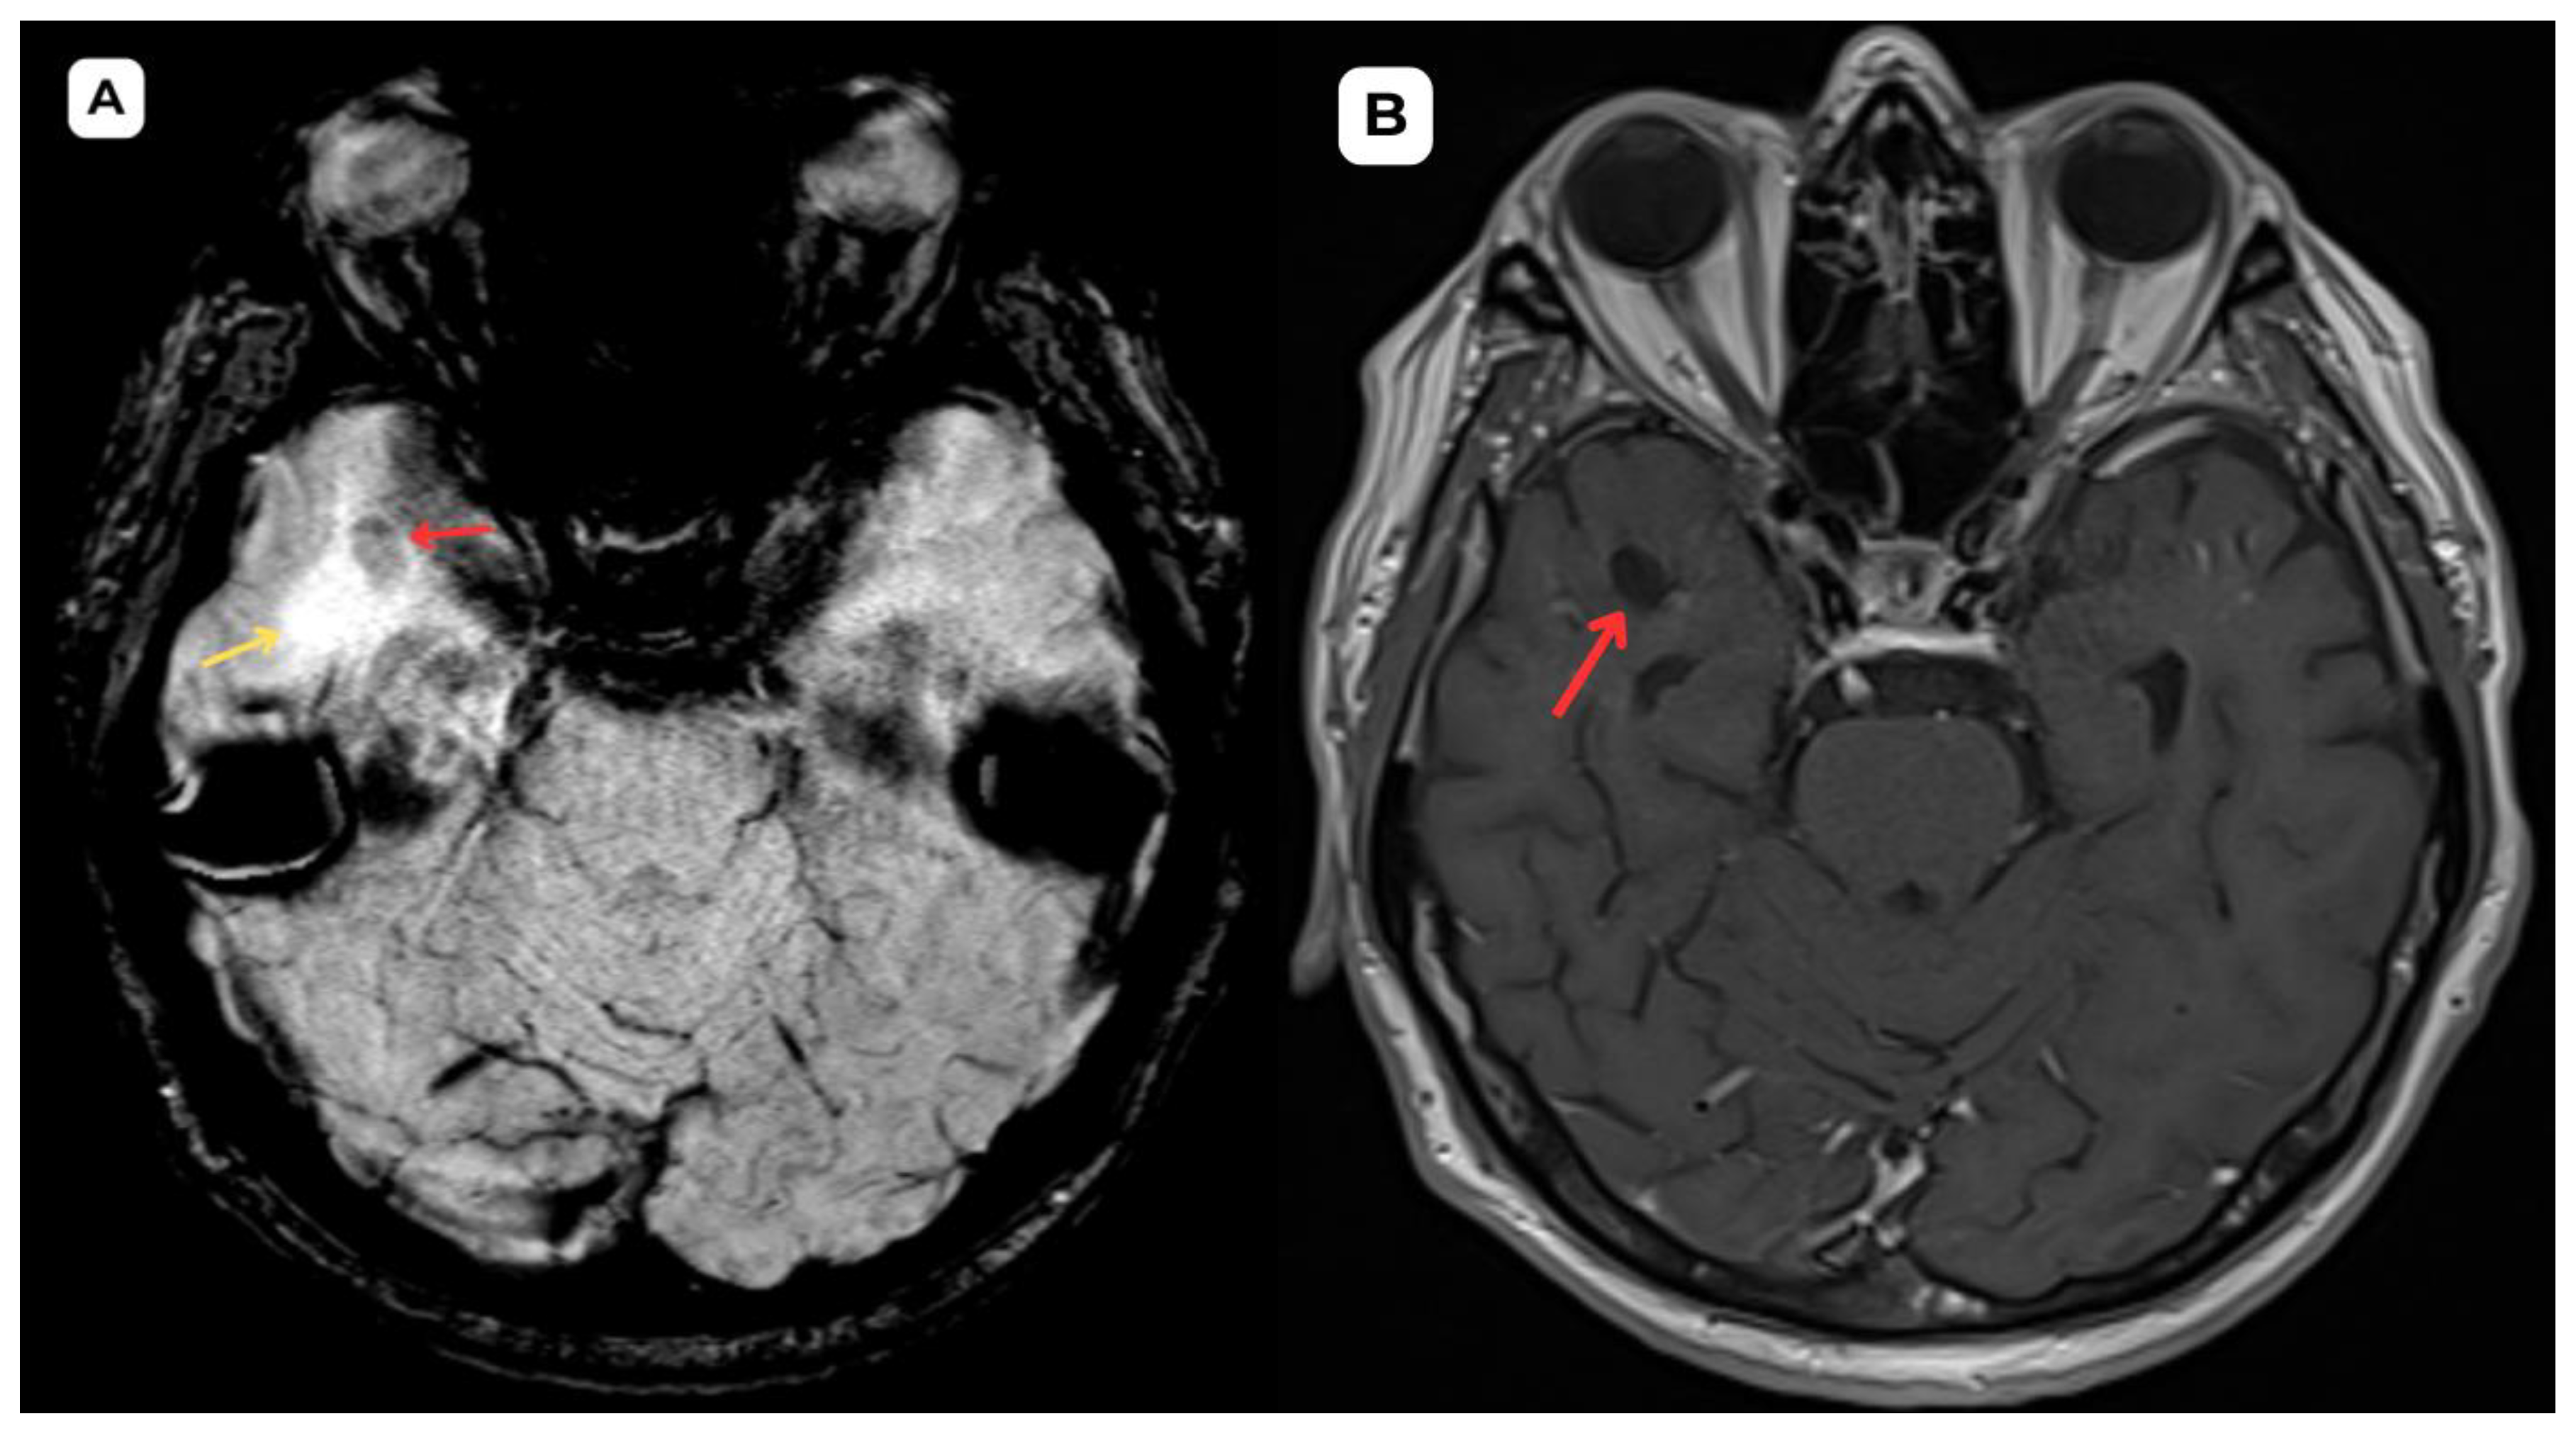

Figure 5. Accompanying second patient: brain MRI of a 67-year-old male. (A): Susceptibility weighted imaging (SWI) axial. A cystic lesion (red arrow) is seen without any hemosiderin or blood products surrounding it. (B): T2-weighted sequence axial, zoomed in, demonstrates better visualization of the very minimal perifocal edema/gliosis (yellow arrow) around the cystic lesion (red arrow) in the white matter. Red arrow—opercular (type IV) perivascular space, yellow arrow—surrounding edema.

Figure 6. Accompanying second patient: One-year follow-up brain MRI of a 67-year-old male. (A): T2-weighted sequence and (B): T2-FLAIR one-year follow-up MRI demonstrates no changes in the cystic lesion (red arrows) and surrounding structures. The minimal perifocal edema or gliosis (yellow arrows) has remained stable; no changes in size or signal intensity can be seen. These findings serve as an important criterion in uncertain cases of PVS; they are likely of a benign nature and consistent with an opercular (type IV) perivascular space. Red arrow—opercular (type IV) perivascular space, yellow arrow—surrounding edema.

These PVS are frequently associated with perifocal edema, likely due to the region’s loose white matter structure and increased interstitial fluid permeability around small penetrating vessels. It should be emphasized that the presence of perifocal edema does not necessarily indicate an active pathological process; it may represent a reactive or structural phenomenon without clinical significance, particularly in elderly individuals [3,4]. Perifocal edema surrounding an opercular perivascular space can range from minimal to very profound and is found in roughly 80% of cases of type IV PVS [5]. In this case, the first patient had more pronounced perifocal edema in both the initial MRI examination (Figure 1 and Figure 2) and the one-year follow-up MRI (Figure 3) than the second patient (Figure 4, Figure 5 and Figure 6).

In magnetic resonance imaging, the signal intensity of the opercular perivascular spaces themselves is identical to that of cerebrospinal fluid in all sequences—hypointense on T1W1 and FLAIR, hyperintense on T2W1, and the ADC value corresponds to cerebrospinal fluid [6,7]. In both of these cases, MRI images were acquired with the Siemens “MAGNETOM Sola” 1.5T system. In both cases, cerebrospinal fluid signal is visible in all MRI sequences. In the images, these PVS are located very close to the branches of the middle cerebral artery, which come into contact with the cerebral cortex, with MRI showing regional cortical thinning in the brain [6,7].

In MRI imaging, opercular perivascular spaces can also be differentiated based on their appearance: round, oval, or tubular, well-defined cystic structures that do not contain calcifications, hemorrhagic elements, or high-protein content structures. In both cases, opercular perivascular spaces appear round (Figure 1, Figure 2, Figure 3, Figure 4, Figure 5 and Figure 6). These formations do not enhance with contrast, which also helps to distinguish them from other pathologies. In both of the cases no contrast enhancement was seen (Figure 1, Figure 2, Figure 3, Figure 4, Figure 5 and Figure 6). It is important to highlight the pathognomonic feature—visualization of the perforating central artery of the perivascular space—using TOF combined with 3D CISS sequences [8].